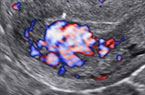

Pseudo anévrisme intra-utérin - Doppler énergie Pseudo anévrisme intra-utérin - Doppler énergie Pseudo anévrisme intra-utérin - Doppler énergie

Pseudo anévrisme intra-utérin d'origine traumatique Pseudo anévrisme intra-utérin d'origine traumatique Pseudo anévrisme intra-utérin d'origine traumatique

Anévrysme utérin post révision utérine pour rétention trophoblastique Anévrysme utérin post révision utérine pour rétention trophoblastique Anévrysme utérin post révision utérine pour rétention trophoblastique